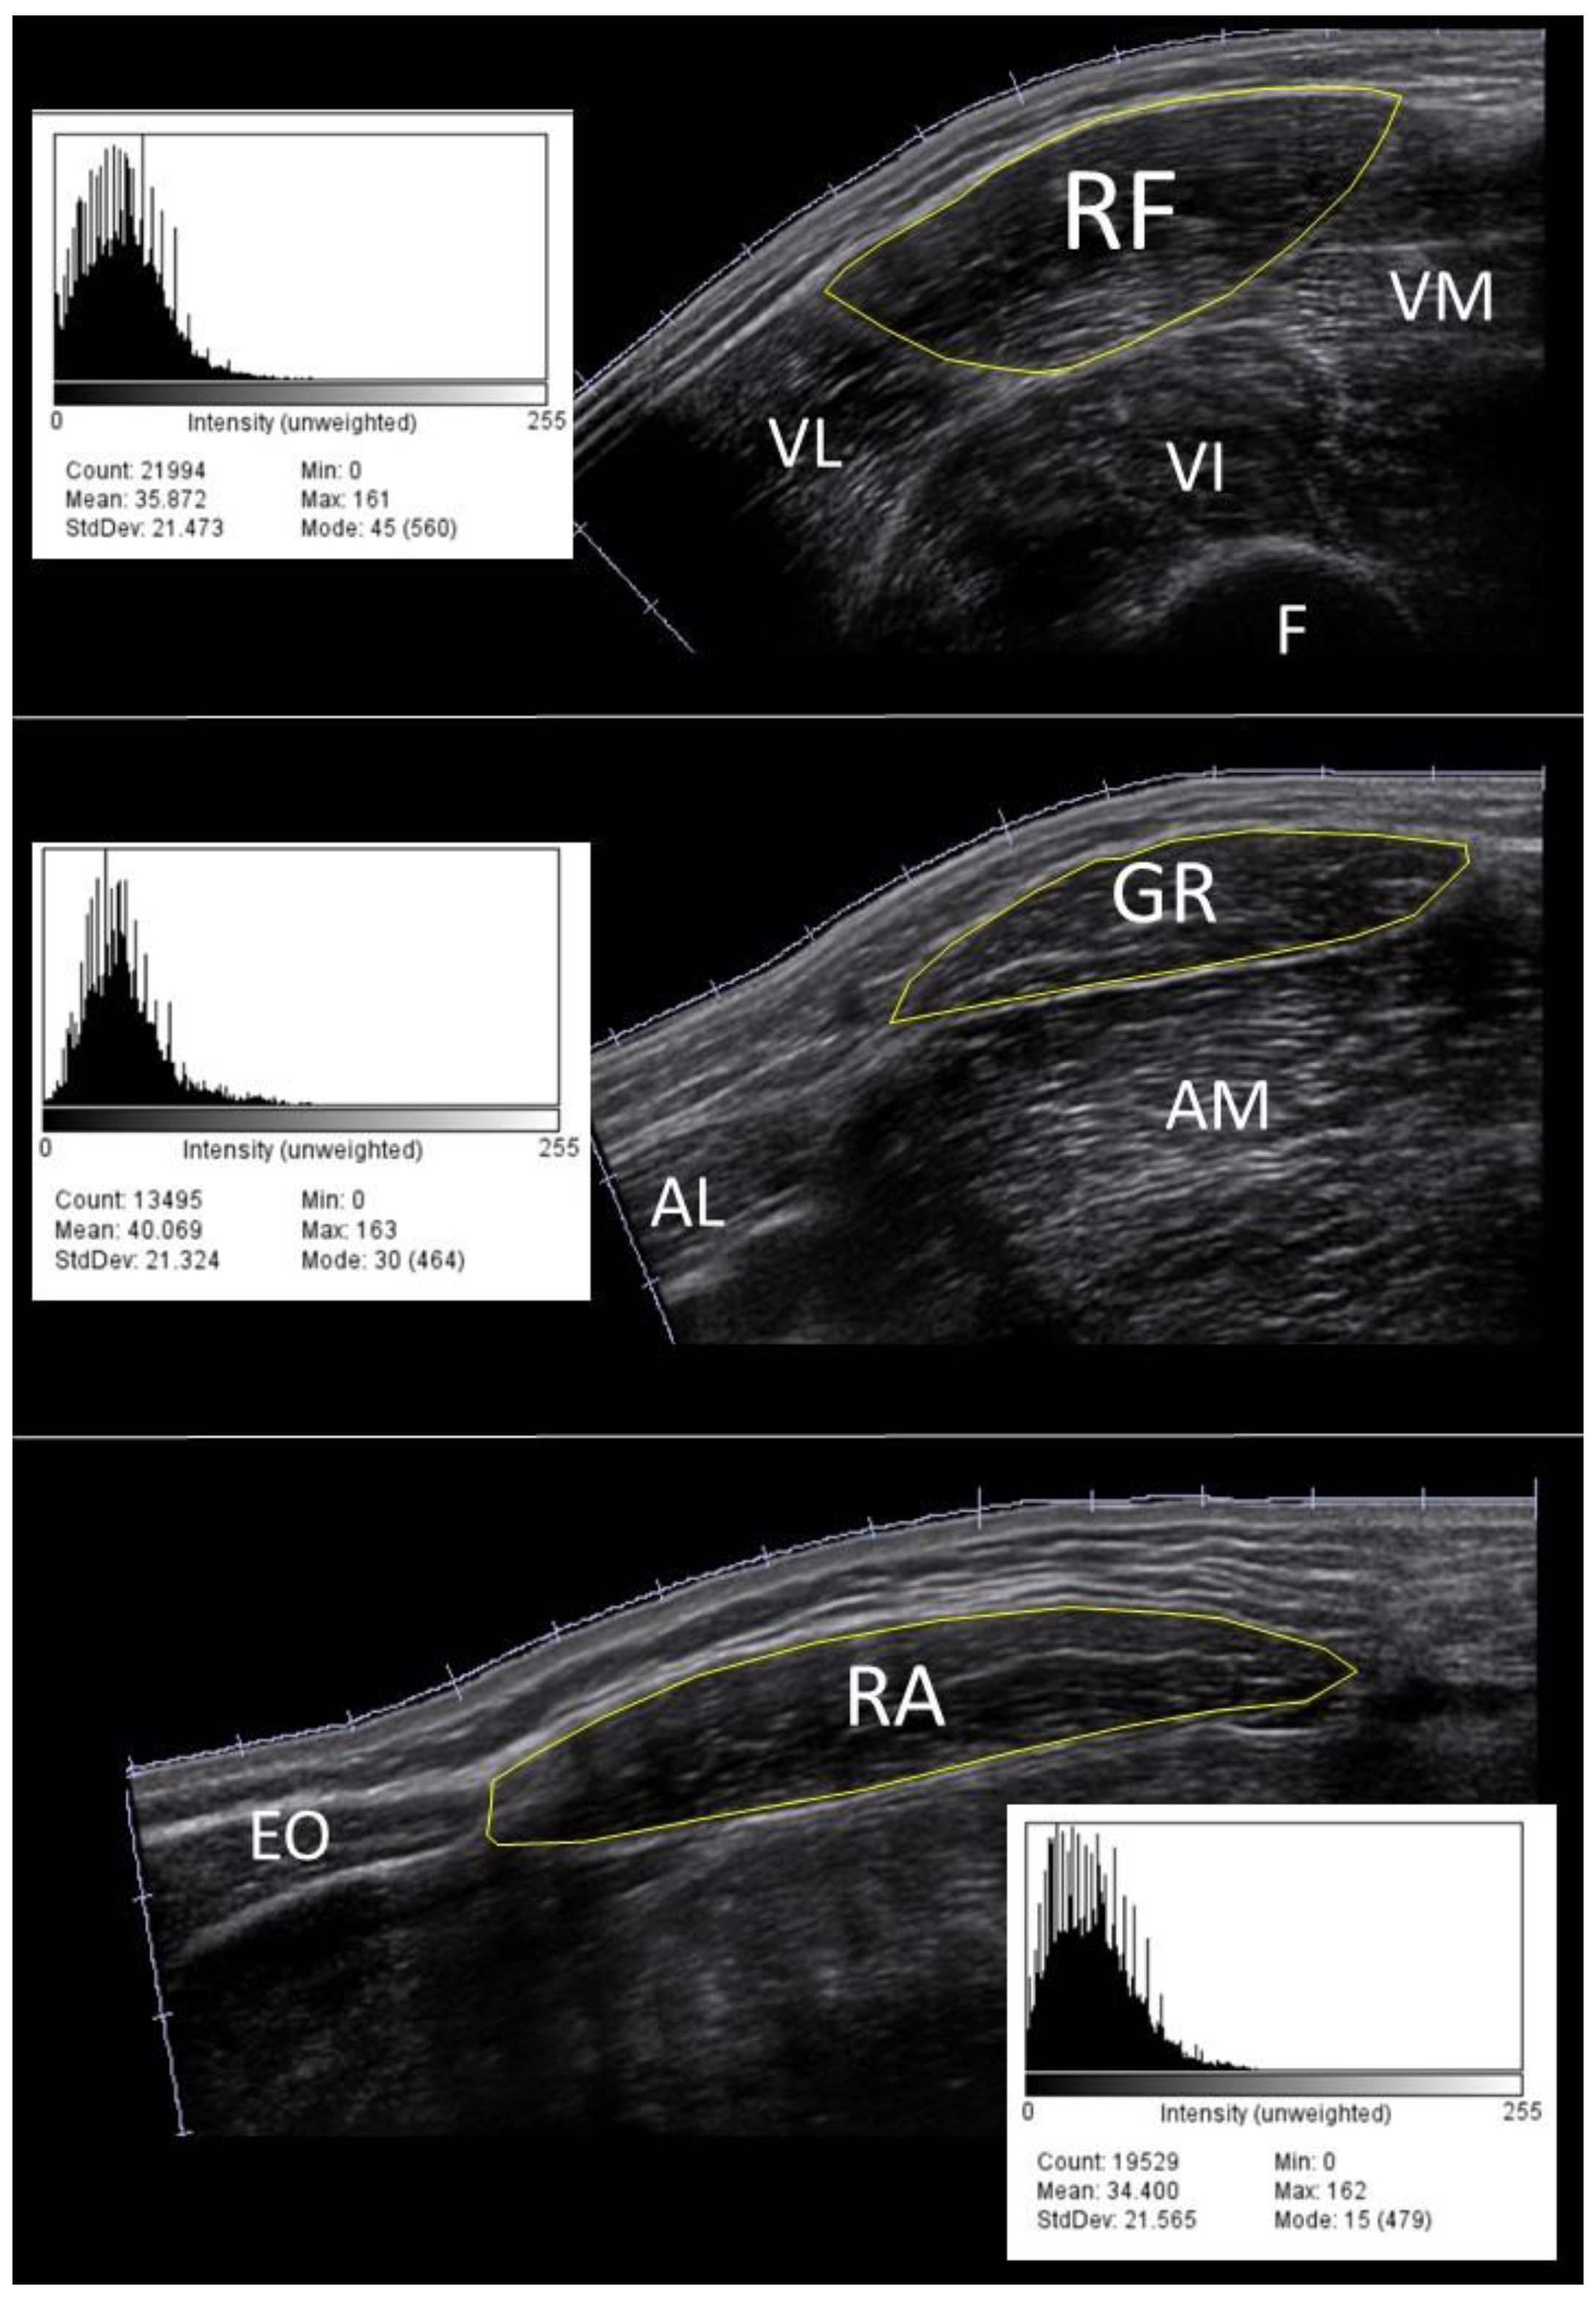

All acquired images were stored on a USB drive and imported to another computer for post-processing analysis. Before data extraction, through a first visual check, a dozen images were discarded and scanned again due to the presence of artifacts, caused by generic software issues. The cross-sectional area of the muscle was manually traced in each image using ImageJ (National Institutes of Health, Bethesda, MD, USA). A region containing as much of the muscle as possible, avoiding intermuscular fascia and surrounding tissues was selected [28]. The EI value of the cross-sectional area was computed based on the histogram of the image (8-bit resolution, resulting in an arbitrary unit (AU) between 0 and 256, where black=0 and white=255, Figure 1).

Figure 1. Example of the echo intensity histograms of rectus femoris (top), gracilis (middle) and rectus abdominis (bottom) muscle scans in a 40 year old male volunteer using the default setup. RF = rectus femoris, VM = vastus medialis, VL = vastus lateralis, VI = vastus intermedius, F = femur, GR = gracilis, AM = adductor magnus, AL = adductor longus, RA = rectus abdominis, EO = external oblique.